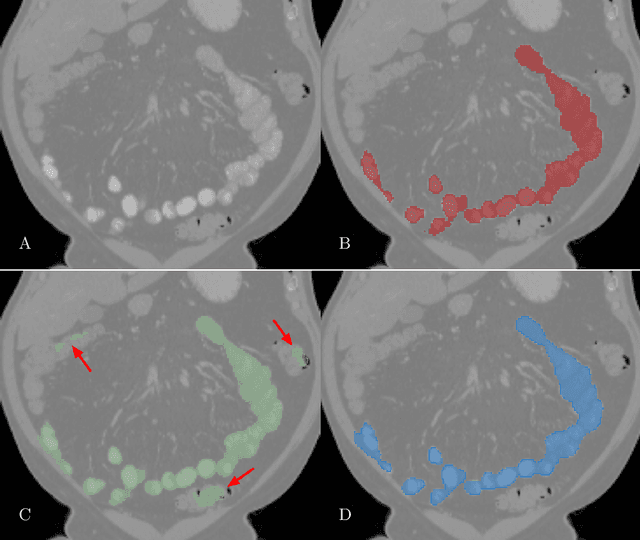

Abstract:We propose a method to incorporate the intensity information of a target lesion on CT scans in training segmentation and detection networks. We first build an intensity-based lesion probability (ILP) function from an intensity histogram of the target lesion. It is used to compute the probability of being the lesion for each voxel based on its intensity. Finally, the computed ILP map of each input CT scan is provided as additional supervision for network training, which aims to inform the network about possible lesion locations in terms of intensity values at no additional labeling cost. The method was applied to improve the segmentation of three different lesion types, namely, small bowel carcinoid tumor, kidney tumor, and lung nodule. The effectiveness of the proposed method on a detection task was also investigated. We observed improvements of 41.3% -> 47.8%, 74.2% -> 76.0%, and 26.4% -> 32.7% in segmenting small bowel carcinoid tumor, kidney tumor, and lung nodule, respectively, in terms of per case Dice scores. An improvement of 64.6% -> 75.5% was achieved in detecting kidney tumors in terms of average precision. The results of different usages of the ILP map and the effect of varied amount of training data are also presented.

Abstract:Finding small lesions is very challenging due to lack of noticeable features, severe class imbalance, as well as the size itself. One approach to improve small lesion segmentation is to reduce the region of interest and inspect it at a higher sensitivity rather than performing it for the entire region. It is usually implemented as sequential or joint segmentation of organ and lesion, which requires additional supervision on organ segmentation. Instead, we propose to utilize an intensity distribution of a target lesion at no additional labeling cost to effectively separate regions where the lesions are possibly located from the background. It is incorporated into network training as an auxiliary task. We applied the proposed method to segmentation of small bowel carcinoid tumors in CT scans. We observed improvements for all metrics (33.5% $\rightarrow$ 38.2%, 41.3% $\rightarrow$ 47.8%, 30.0% $\rightarrow$ 35.9% for the global, per case, and per tumor Dice scores, respectively.) compared to the baseline method, which proves the validity of our idea. Our method can be one option for explicitly incorporating intensity distribution information of a target in network training.